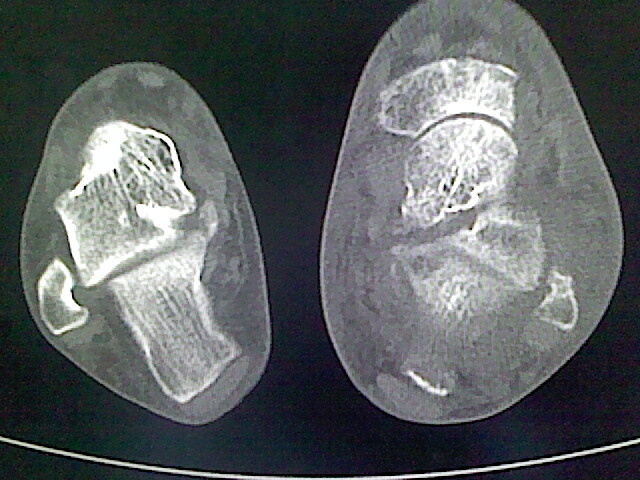

标题: CT16814:男,76岁,左小腿疼痛,不能站立 大家给看看 [打印本页]

男,76岁,左小腿疼痛,不能站立

本例骨质改变主要表现为滑膜或韧带区的骨侵蚀融解(胫腓联合区骨质破坏无硬化边),距骨后部骨质破坏区有硬化边及死骨样改变.所以,本例考虑关节结核可能性大,绒毛膜结节性滑膜炎多发于中年,且极少见于膝髋以外的关节,骨质硬坏也以压陷吸收为主,有明显的硬化边,骨膜增生呈结节状(可以mr鉴别),所以本例暂除外.

另不除外可引起相似表现的其他炎症如布氏杆菌性关节炎等